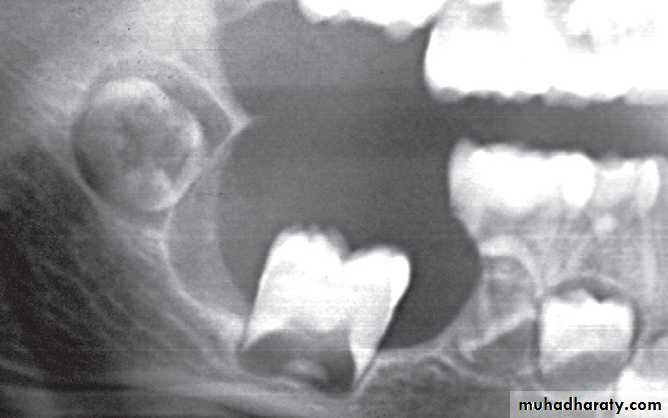

Size

There are very few size restrictions for a particular lesion, but the size may aid in the differential diagnosis. For instance, when differentiating between a dentigerous cyst and a hyperplastic follicle surrounding the coronal portion of a tooth, size may be considered a determining factor. Because dentigerous cysts have growth potential, they are often much larger than a hyperplastic follicle.Step 2: Assess Periphery and Shape

1-Circular or fluid-filled shape, is characteristic of a cyst.2-Scalloped shape is a series of contiguous arcs or semicircles that may reflect the mechanism of growth. This shape may be seen in cysts (e.g., keratocystic odontogenic tumors), cyst like lesions (e.g., simple bone cysts), and some tumors. Occasionally, a lesion with a scalloped periphery is referred to as multilocular.

Displacement of teeth is seen more commonly with slower growing, space-occupying lesions.Lesions with an epicenter above the crown of a tooth (i.e., follicular cysts and occasionally odontomas) displace the tooth apically.